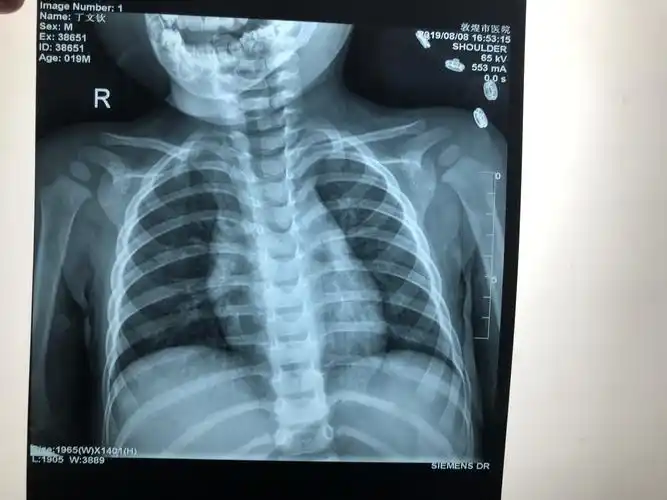

一岁半小儿锁骨骨折治疗一例.

小孩锁骨骨折